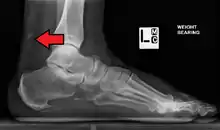

Calcification from dermatomyositis

X-Ray of the knee in a person with dermatomyositis.

Magnetic resonance imaging may be useful to guide muscle biopsy and to investigate involvement of internal organs;[14] X-ray may be used to investigate joint involvement and calcifications.[15]